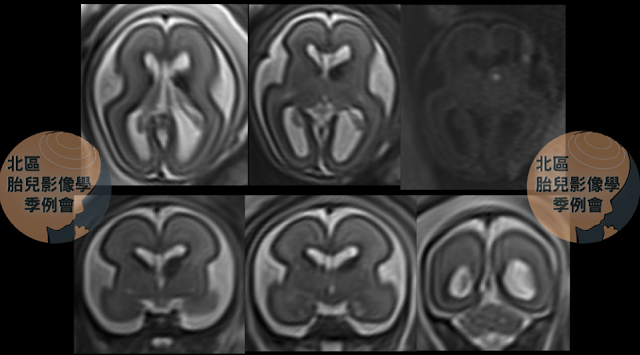

2025年7-8月-2/6:【台兒知識庫】胎兒生發基質出血germinal matrix hemorrhage(GMH)的診斷與追蹤:一則臨床案例分享

![]() |

| (圖一)妊娠23週超音波影像顯示左側尾狀核與丘腦交界處(caudothalamic groove)有一高回音病灶。(台兒診所提供) |

胎兒腦內出血(intracranial hemorrhage, ICH)是產前診斷中的一大挑戰,由於不同及未知的潛在病因影響,可能呈現截然不同的歷程及預後。以下分享一則胎兒生發基質出血germinal matrix hemorrhage(GMH)的臨床案例,呈現其影像學發現、診斷過程及追蹤結果。

| (圖二)妊娠23週1天胎兒核磁共振影像顯示左側尾狀核丘腦交界處有約 8mm大T2 加權影像的低訊號變化 及T1 加權影像 的高訊號變化。(榮科醫學影像中心提供) |